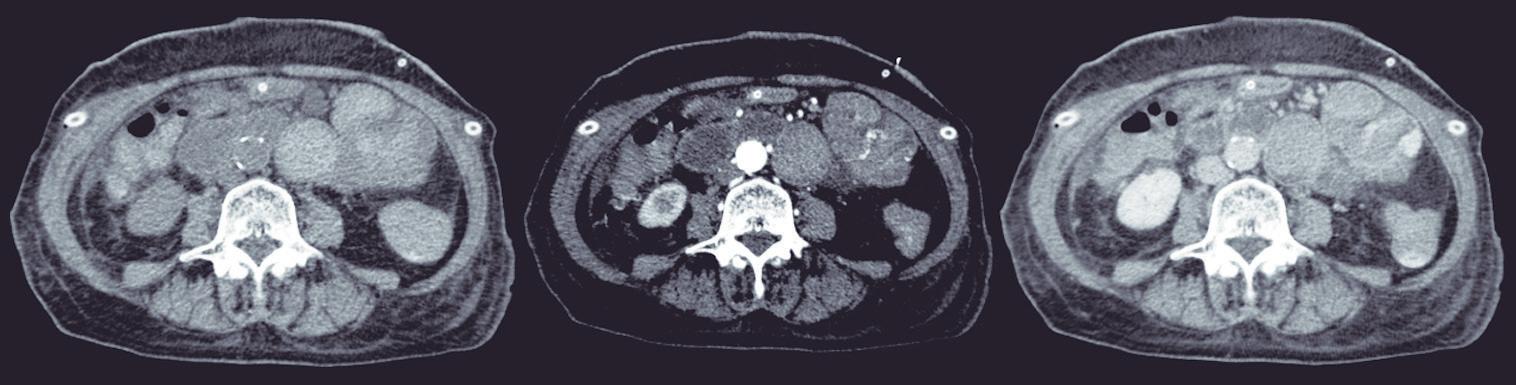

La endoscopía superior es un procedimiento fundamental para el diagnóstico, la evaluación de la respuesta al tratamiento y el monitoreo a largo plazo de la actividad de la EEo. Los hallazgos endoscópicos típicos incluyen edema (reducción de vascularidad), anillos esofágicos fijos, exudados blancos, surcos longitudinales, estenosis, estrechamiento de la luz esofágica, friabilidad de la mucosa (mucosa en papel crepé) y una consistencia firme de la mucosa al realizar biopsias (signo de “tracción" o "resistencia”) en pacientes con fibrosis (Figura 1). Estos hallazgos no son patognomónicos y no constituyen un criterio diagnóstico; sin embargo, cuando se evalúa de forma cuidadosa, en la gran mayoría de los casos se pueden observar.19-21

En el panel A se observa un esófago con edema difuso y pliegues longitudinales; en el panel B se aprecia edema con pliegues y exudados blanquecinos; en el panel C se evidencia un estrechamiento luminal acompañado de anillos esofágicos y exudados; y en el panel D se muestra un desgarro mucoso posterior a la dilatación con bujía de Savary, hallazgo esperado tras este procedimiento terapéutico.

Figura 1. Características endoscópicas de la esofagitis eosinofílica